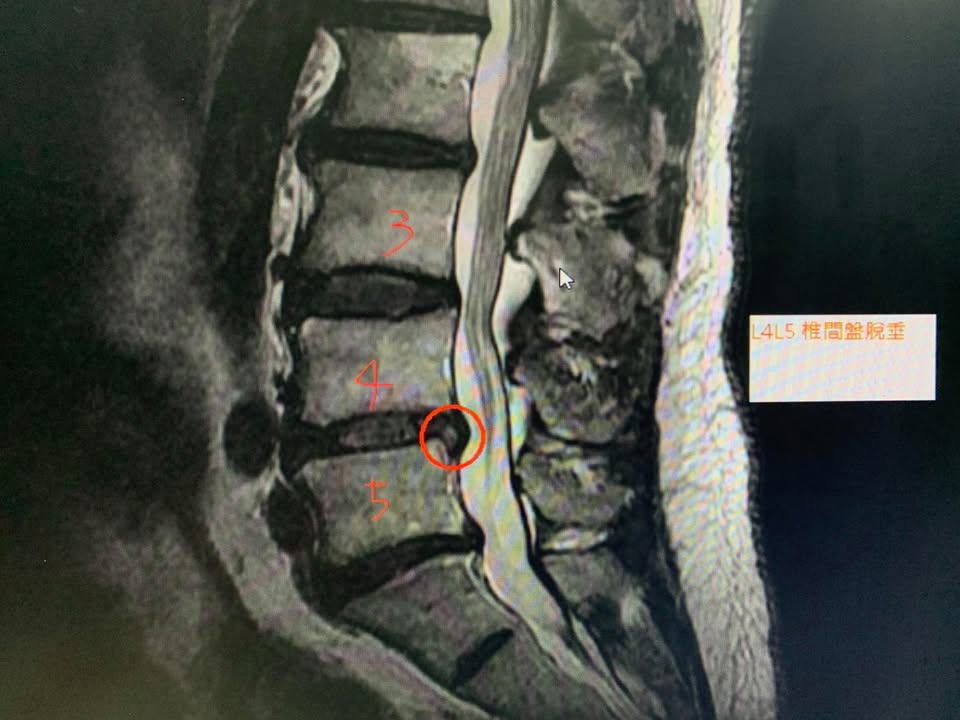

羅大哥抱怨右側腰痛連屁股,右側屁股最痛,躺著比較容易痛,坐著跟站著比較刺痛,剛開始非常痛,休息一陣子比較好,拉腰兩個月沒特別大改善,今年八月十二拍MRI,證實HIVD腰椎第四第五椎間盤突出,合併右側多裂肌萎縮,神外醫師建議可以考慮開刀,但患者畏懼開刀

✅診斷:椎間盤突出壓迫神經根

多裂肌萎縮